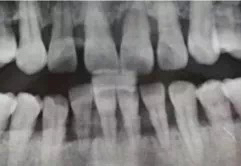

这位中年女士因为牙周炎导致许多牙齿晃得厉害,平日咀嚼都成问题,实在疼得受不了才来看牙。

牙龈萎缩,牙齿松动

朋友早就建议她洗牙,她不敢,怕洗出血,洗完牙缝变大、牙齿松动。